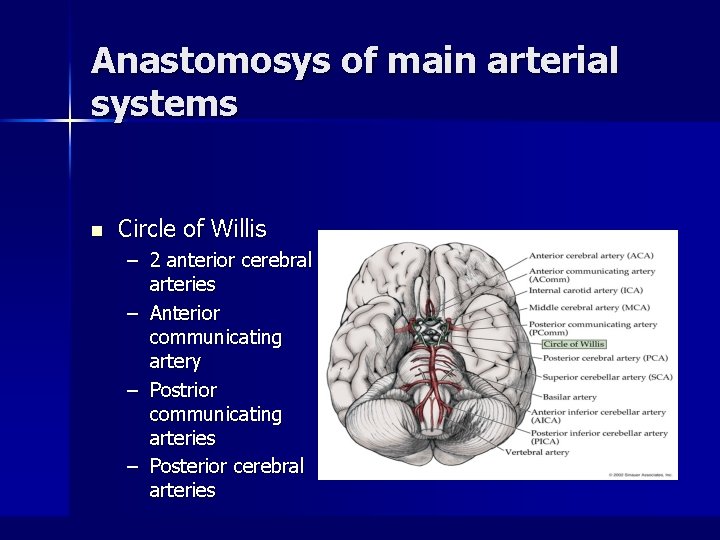

Anastomosys of main arterial systems n Circle of Willis – 2 anterior cerebral arteries – Anterior communicating artery – Postrior communicating arteries – Posterior cerebral arteries

Anatomosys n n Extracranial Intracranial Compensation via 1. Aortic arch 2. Subclavian – vertebral aa 3. Internal – external carotis communications 4, 5 Willis polygone 6. Cortical and meningean anastomosys